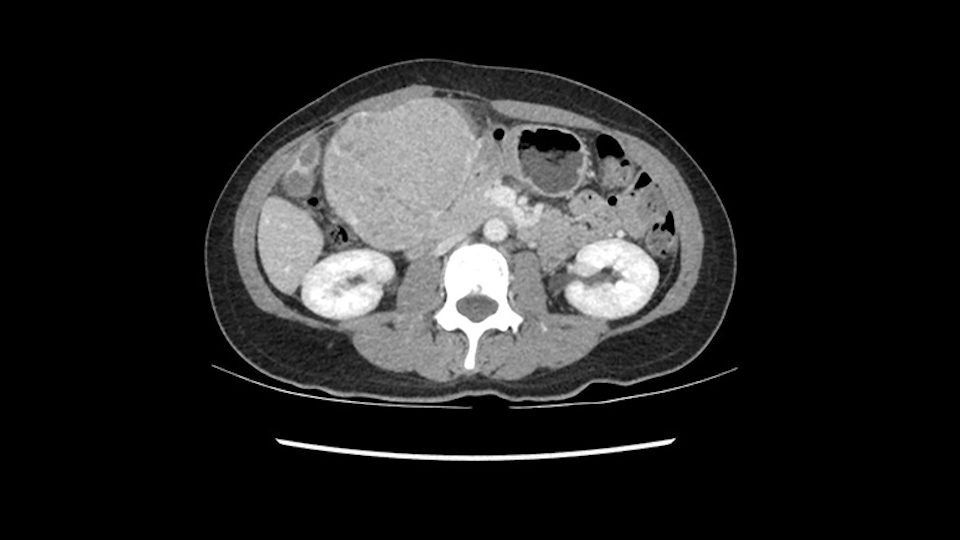

So the issue with regards to resection. A left sided tumor. I believe I can see the falciform ligament right here so we’re looking at a resection of Segments 2, 3 of the left lobe of the liver. The left portal vein is right there. I think we’ll be wiser to take the left portal vein and therefore get well into Segment 4 and do a left hemihepatectomy. Certainly, one does not need to take the middle hepatic vein; it’s miles from the tumor.

We note that the tumor is pushing on the gallbladder but I think that’s probably external for the most part. I think that’s extrahepatic. I believe that Segment 4b is probably free of tumor. I’d have to say that it's tempting, particularly looking at the coronals, to consider a very limited resection. Where you’d just chip it off the bottom of Segment 3 and do a limited Segment 3 resection. I’d be concerned about the oncologic margins. I believe that the best oncologic operation will be to take the left portal vein to get this. Certainly, she’s got plenty of liver and she’d be able to sacrifice Segments 2-3 of the left lobe of the liver. It’s not necessary to take too much of thus of Segment 4a. But once one takes the portal vein, that will be compromised. So I would do a left hemihepatectomy on this woman.

So I have to say that I would do this open, not laparoscopically because of the size of the tumor itself. Upper abdominal incision. Almost certainly, we’d be able to flip this very exophytic lesion up. Intraoperative ultrasound will show the relationship of the tumor and the left portal vein but the dissection at the base of the liver, as I look at things here, I can see the left hepatic artery which sneaks up to the left of the portal vein, should be out of harm’s way so I can take the Segment 2-3 left hepatic artery. The left portal vein is somewhat compressed. But by the time you pull the liver up a bit, you’ll be able to pull that left portal vein out to length and get a good margin on it.

My plan would be to leave the caudate lobe intact. You usually have to divide the caudate branches. I can see one of the caudate branches here coming off the left portal vein. You usually have to take that to get adequate length although you might be able to divide the portal vein past that left caudate branch.

The transection line will be a little more obvious. There’s a little patch of focal fat here in Segment 4b but we’ll describe the transection line probably through the mid portion of Segments 4a and b up to the top. Up at the top, the left hepatic vein can be taken. There’s a Segment 3 vein or the so-called falciform vein it’ll be rudimentary so I think we’ll be able to get around the left hepatic vein and leave the middle [hepatic] vein intact because it’s free of tumor.

The tumor is so close to the falciform ligament, I had a question mark about the Segment 4b relation between segment 4b and segment 3. In a normal resection of segment 2 and 3, we would be keeping on the left side of the falciform ligament and start getting segment 3 and 2 portal pedicles but in here its getting so close. So oncologically, 4b should be checked during the OR.

What kind of procedure can we plan for this patient? It obviously has to be a left hemihepatectomy because most of the lesion is actually in Sg4. Can we do something which is less than a hemihepatectomy and just do only a segmental resection? The answer to that is that this vascular supply, if you are trying to ligate only the portal venous pedicle to the Segment 4, it is very close to the tumor and you will end up not having not a great margin as far as tumor resection is concerned so I would recommend a left hemihepatectomy and not just a partial or segmental resection. You can also see that it is crossing the falciform line and going on to Segment 2 and 3 so trying to do anything less than a left hemihepatectomy may not give the right kind of margins which we need for this tumor. Fortunately for us, the contours of the liver, which are very important to see in a Hepatitis B patient, there are no cirrhosis which I can see. The normal liver functions indicate that it's a well compensated Hepatitis B.

Now let’s look at some specific anatomical points for planning this surgery. First thing you see when you see a left hemihepatectomy is that where is the left portal vein and the right portal vein branching? And what is the stump of the left portal vein available for you for ligation? In this particular case, you’ll find that there’s overhanging of the tumor but left portal vein pedicle is sufficiently available for us for ligation.

So in planning for this operation, as I look at the scans, I first visualize the arterial phase and I can see that there’s are a lot of big feeding arteries to this large tumor. Likely all the right side vessels feeding the right side of the liver: right hepatic artery and likely the Segment 4 artery are spared from the tumor. It’s likely the left hepatic artery is ramificating and giving feeding arteries to this tumor. It certainly looks like a large mass that its compressing other structures like the cava, the pancreas, the stomach; but I think there’s a plane and we can see that better in the venous phase. There’s a plane of separation between the gallbladder, the pancreas, the cava, that this tumor is abrupting but likely not invading. Usually, these masses actually don’t invade at that level and basically are pushing the tissues and once you open, you’re able to separate the tumor. Sometimes there’s some adhesions but you can actually separate and there’s usually no invasion.

The other thing I would do in this case is to certainly to assess the coronal phase as we can see in the coronal phase, this tumor looks like it's growing from Segment 3, and again I don’t think there’s involvement of the right side of the liver or even on Segment 4.